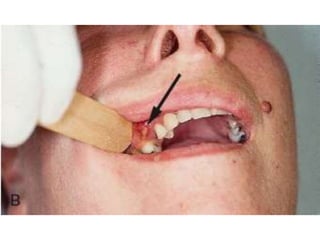

Pericoronitis

Pain, foul taste or odour

Involves erupting tooth, often 3rd molar

Inflammation of the gingival tissue overlying

the erupting crown

Drainage, antibiotics, NS rinses